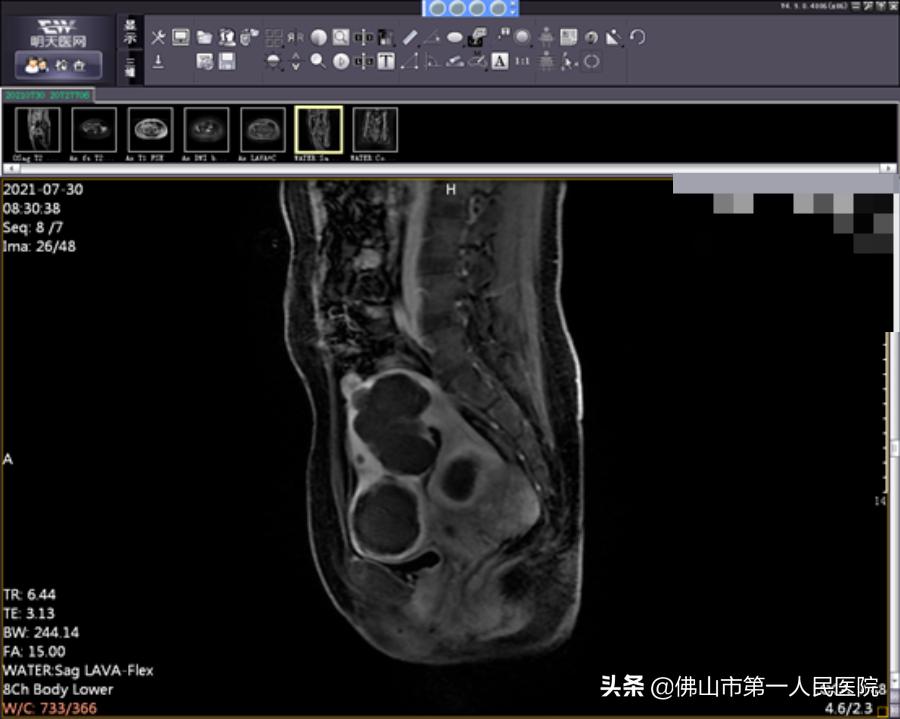

术后图像(海扶使肿瘤组织发生凝固性坏死)

海扶刀手术时长2小时50分钟,治疗时间25分钟。王女士表示术中无明显不适,术后数小时后就能下床正常活动。术后复查磁共振提示消融效果满意,术后月经量正常,术后复查MRI肌瘤消融满意。